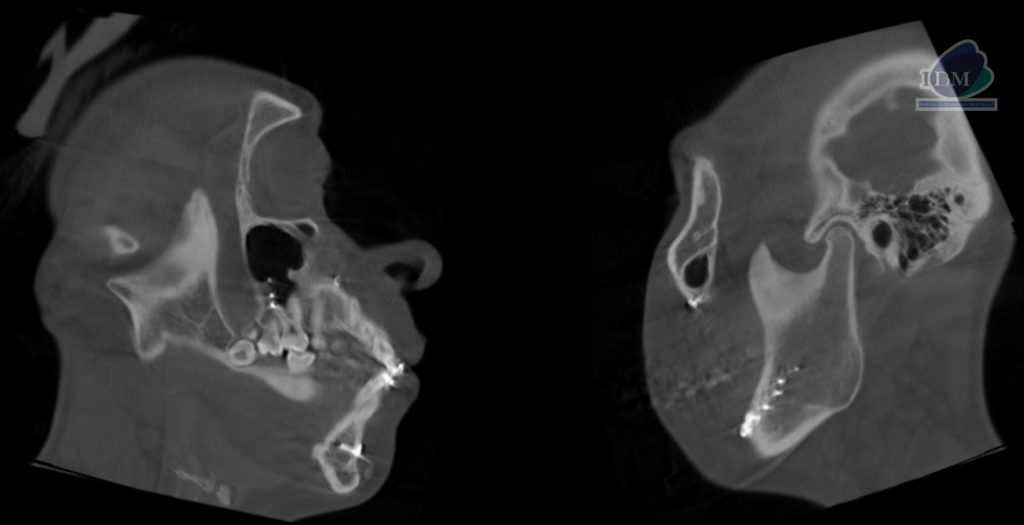

Así mismo en la tomografía volumétrica de haz se confirma una elongación por parte de la apófisis coronoides de lado derecho, extendiéndose sobre el borde superior del arco cigomático de ese mismo lado.

CORTES SAGITALES

- Hiperplasia de apófisis coronoides de lado derecho.